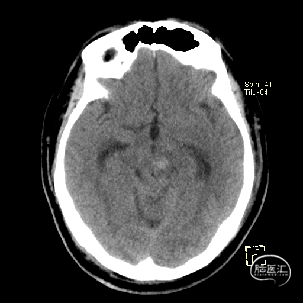

术后当天CT

术后1周CT复查